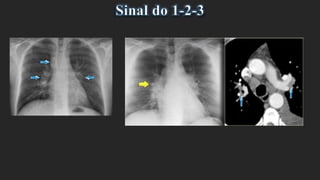

Sinal do 1-2-3:

Padrão clássico na sarcoidose que consiste na combinação de adenopatias

- paratraqueais direitas (1),

- hilares direitas (2) e

- hilares esquerdas (3).

A – Radiografia do tórax de frente mostrando aumento simétrico das

dimensões e da densidade dos hilos, que apresentam contornos

lobulados.

Alargamento do mediastino superior em sede para-traqueal direita. Estes

achados são compatíveis com o sinal do 1-2-3

Sarcoidose

Confirmado por TC torácica - adenopatias para traqueais direitas (B) e

hilares bilaterais (C)